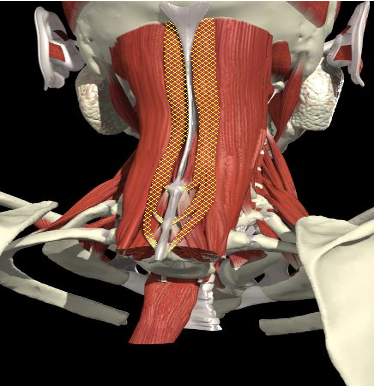

Extensor Group

Splenius Capitis

Splenius Cervicis

Semispinalis Capitis

Longissimus Capitis

Spinalis Capitis

(Erector Spinae)

Semispinalis Cervicis

Layer 1

Layer 2

Layer 3

- Working together extend the neck

Function

- Tilt the head to the same side – splenius capitis, cervicis

- Turn head to

- Same side – lateral muscles insert into mastoid

- Splenius capitis, cervicis, Longissimus capitis

- Opposite side - medial muscles insert into occiput